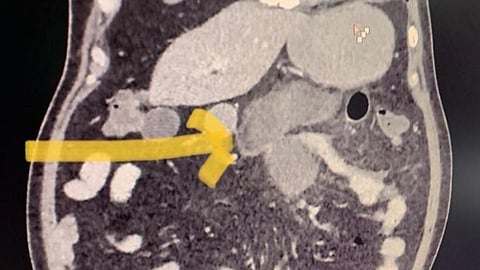

सुरुवातीला त्या दोघांच्याही पोटात खूप दुखत होतं. अखेर डॉक्टरांनी त्यांना सीटी स्कॅन करण्याचा सल्ला दिला आणि त्यामध्ये दोघांच्याही छोट्या आतड्यांना म्युकरमायकॉसिसमुळे छीद्र पडल्याचं दिसून आलं आहे. हा ब्लॅक फंगसचा दुर्मिळ प्रकार असल्याचं सांगण्यात येत आहे. त्यांच्यावर आता तातडीने उपचार सुरु करण्यात आले आहेत.